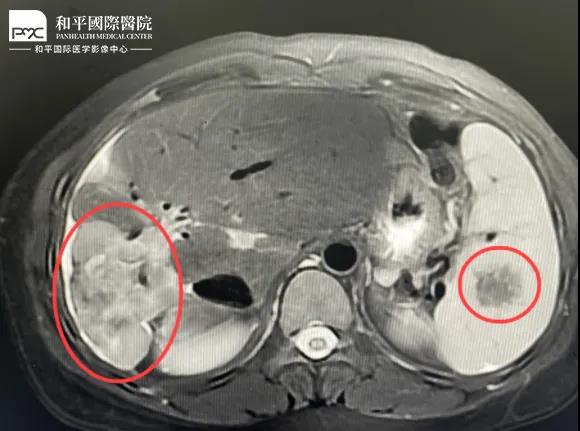

檢查結(jié)果對(duì)于這家人而言猶如晴天霹靂,經(jīng)核磁共振等相關(guān)檢查,當(dāng)?shù)蒯t(yī)生懷疑是肝癌,建議手術(shù)治療。悲痛中,家人們對(duì)這樣的結(jié)果表示無法接受,想要多去幾家醫(yī)院看看,為了進(jìn)一步確診,王小姐來到我院醫(yī)學(xué)影像中心進(jìn)行檢查,事情竟發(fā)生了戲劇性反轉(zhuǎn)。

根據(jù)影片分析,結(jié)合王小姐有系統(tǒng)性紅斑狼瘡的病史,長期服用激素,免疫力低下,近期又有低熱盜汗的癥狀,影像中心執(zhí)行主任侯文杰初步判斷王小姐是得了肝結(jié)核,并不是肝癌!

由于肝結(jié)核是臨床非常少見的病例,單靠影像診斷是很難診斷正確的,在侯主任的建議下,王小姐做了穿刺活檢,診斷結(jié)果的確是肝結(jié)核。